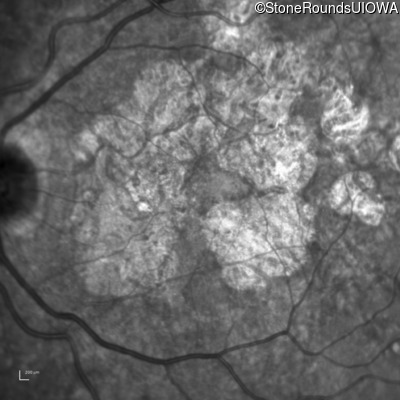

Infrared Fundus Photograph - Right - 20/150

Exemplar

Infrared Fundus Photograph - Left - 20/70